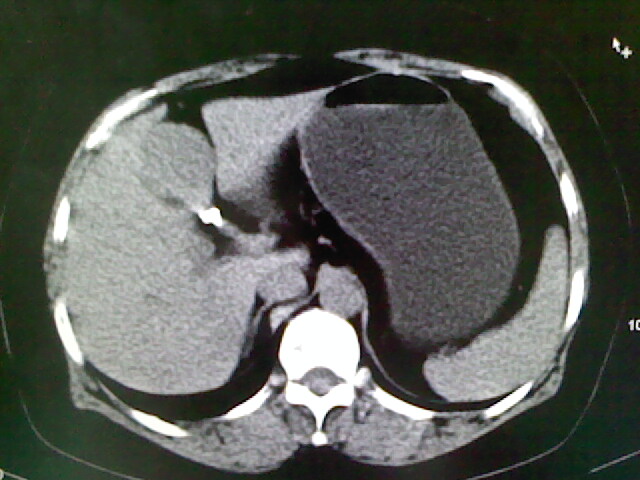

以下是引用卜一在2009-4-2 13:26:00的发言:[br]胆囊颈部结石伴胆囊炎!另:建议增强,待除外肝内占位及胆囊占位!

以下是引用liaoqiang在2009-4-2 16:23:00的发言:[br]胆囊是否切除?胆囊颈区致密影考虑金属夹?结石?肝脏右叶低密度影,考虑增强。